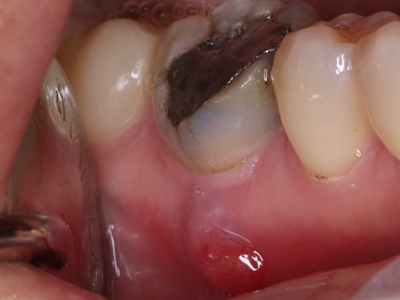

根尖囊肿生长缓慢,病人多无自觉症状。口腔检查可见患牙有龋损或其他非龋性牙体病,或牙冠变色失去光泽。叩诊可有不适感,温度测验患牙无反应。囊肿大小不等,小囊肿不易被发现。囊肿发展较大时,可见根尖部隆起,扪诊时有乒乓球感,这是由于囊肿外围只有一层极薄的骨板存在。大囊肿还可压迫牙根,使邻牙移位。

根尖囊肿可由慢性根尖周肉芽肿或慢性根尖周脓肿等发展而来。因牙根感染、牙髓坏死,进而根尖周形成肉芽肿或脓肿,随后上皮细胞长入其内作为衬里形成囊肿内膜,病牙根尖突入囊肿腔内。增生的上皮团中央发生变性与液化,周围组织液不断渗出,逐渐形成根尖囊肿。

根尖囊肿需有专业医生通过取上颌窦根治术式切除囊肿。若病牙尚稳固,有保留可能,则行根尖切除或根管治疗以避免囊肿再发。否则,应同时拔除病牙。